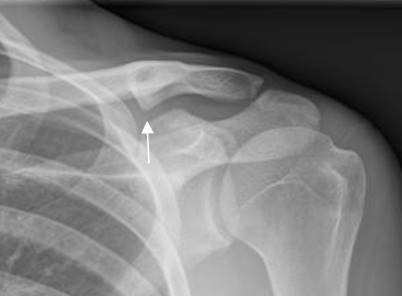

Fig 146. Denervación.

RM axial en T1. Atrofia de los músculos infraespinoso (Flecha gruesa) y subescapular (Flecha delgada), el cual presenta además degeneración grasa. Estos cambios son secundarios a denervación.